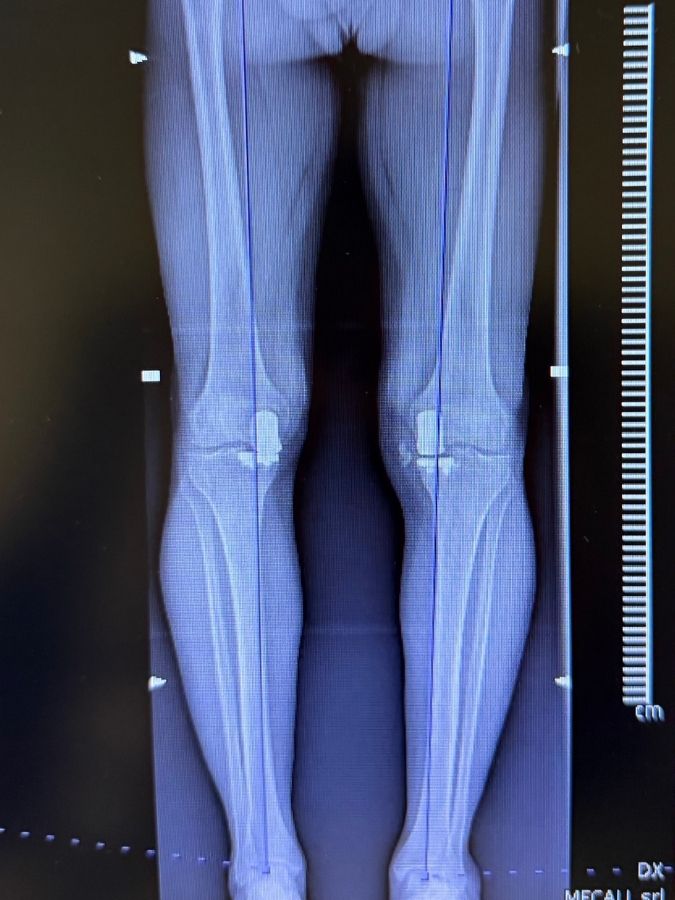

Osteotomie

L’osteotomia correttiva è una tecnica chirurgica che, in caso di usura asimmetrica di un solo compartimento del ginocchio (mediale o laterale), consente di preservare l’articolazione, RIALLINEANDO L’ ARTO e sfruttando la parte ancora sana e funzionalmente valida.

In presenza di deformità causate da varismi o valgismi costituzionali e aumentate dall’usura intra-articolare, l’osteotomia è una soluzione meno invasiva e più conservativa rispetto alla chirurgia protesica, e nella maggior parte dei casi è definitiva: NON SERVIRÀ MAI PIÙ LA PROTESI.